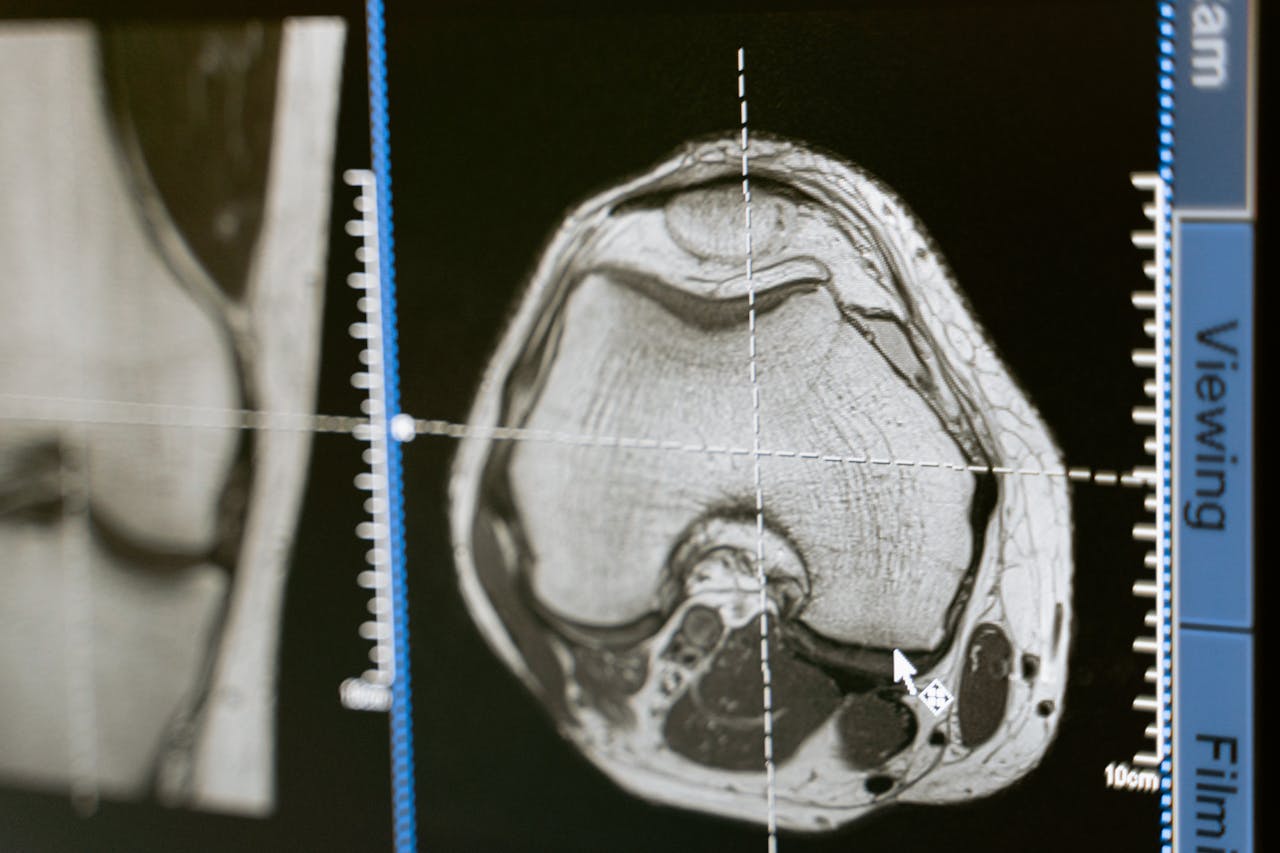

Entretanto, a dor foi apenas o início de um quadro grave, que culminou em sua hospitalização. Exames indicaram que o AVC resultou de um coágulo que atravessou um pequeno orifício em seu coração, conhecido como forame oval patente.

Além de dores de cabeça, a presença de forame oval patente e enxaqueca com aura são fatores de risco adicionais para jovens. O forame oval patente é uma condição cardíaca mais comum do que se imagina, mas raramente diagnosticada antes de um evento vascular.